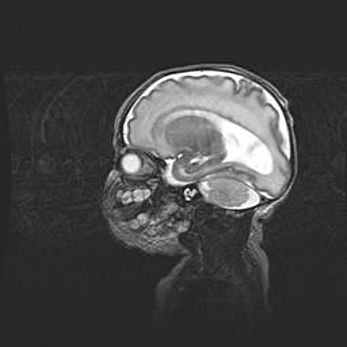

Мальформация Денди-Уокера. Киста задней черепной ямки.

Агенезия мозолистого тела.

Возраст: 2,5 месяца

Вес: 2420 г

Пол: женский

Окружность головы: 37 см

Срок гестации: 32 недели

Мальформация Денди—Уокера — редкий вид патологии ЦНС, представляющий собой врожденный порок развития каудального отдела ствола и червя мозжечка, ведущий к неполному раскрытию срединной (Мажанди) и латеральных (Лушка) апертур IV желудочка мозга. Для этогно синдрома характерна триада симптомов: гипотрофия червя мозжечка и/или полушарий мозжечка, кисты задней черепной ямки, гидроцефалия различной степени. В 70% случаев порок сочетается и с другими аномалиями головного мозга, в частности с агенезией мозолистого тела.